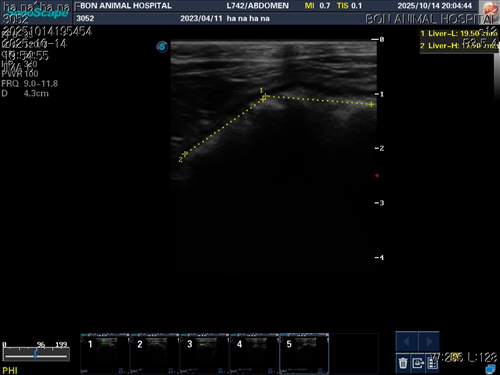

10월 10일 포도를 토해논후로 식욕저하 기력저하가 있어서 동물병원에 방문해서 엑스레이를 찍었는데 우선 지켜보자는 말과 소화제처방과 주사를 맞고 집왔습니다 그 후로도 안먹어서 12일에 동물병원에가서 혈액검사도 하고 수액도 맞았습니다 췌장쪽 수치가 좀 높아서 췌장쪽만 다시 검사했는데 수치는 괜찮았습니다 식욕촉진이랑 소화제처방 받아서 먹이는데 식욕저하도 여전하고 기력이 좀 없고 10일부터 14일까지 대변을 못보고있어서 14일에 병원에 가서 엑스레이랑 초음파를 했는데 장폐색일수도 있다는 말을 들었습니다 초음파상으로는 소장쪽 이물이 의심된다고 하셨어요ㅠ